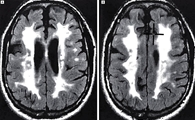

피질하 경색과 백질뇌증을 동반하는 상염색체 우성 뇌동맥질환(Cerebral Autosomal Dominant Arteriopathy with Subcortical Infarcts and Leukoencephalopathy)

CADASIL